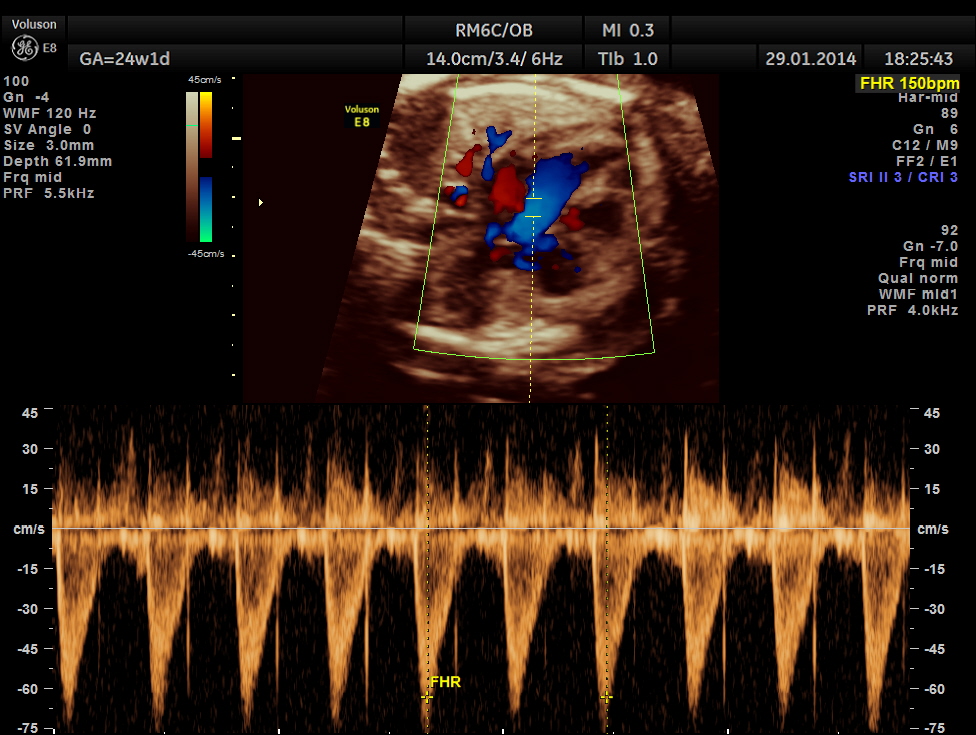

Images of the other organs are given below.